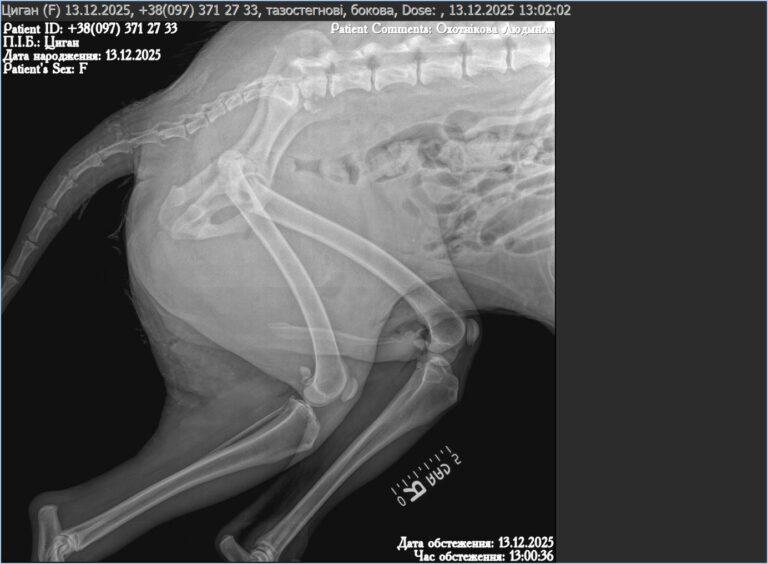

Przed nim RTG, dalsza diagnostyka, ocena obrażeń wewnętrznych. Trzeba sprawdzić, czy nie doszło do złamań, uszkodzeń narządów i krwotoków. Do tego leki przeciwbólowe, antybiotyki, codzienna opieka i obserwacja. Gdy jego stan na to pozwoli, także kastracja — by przerwać spiralę cierpienia, która na ukraińskich ulicach nigdy się nie kończy.